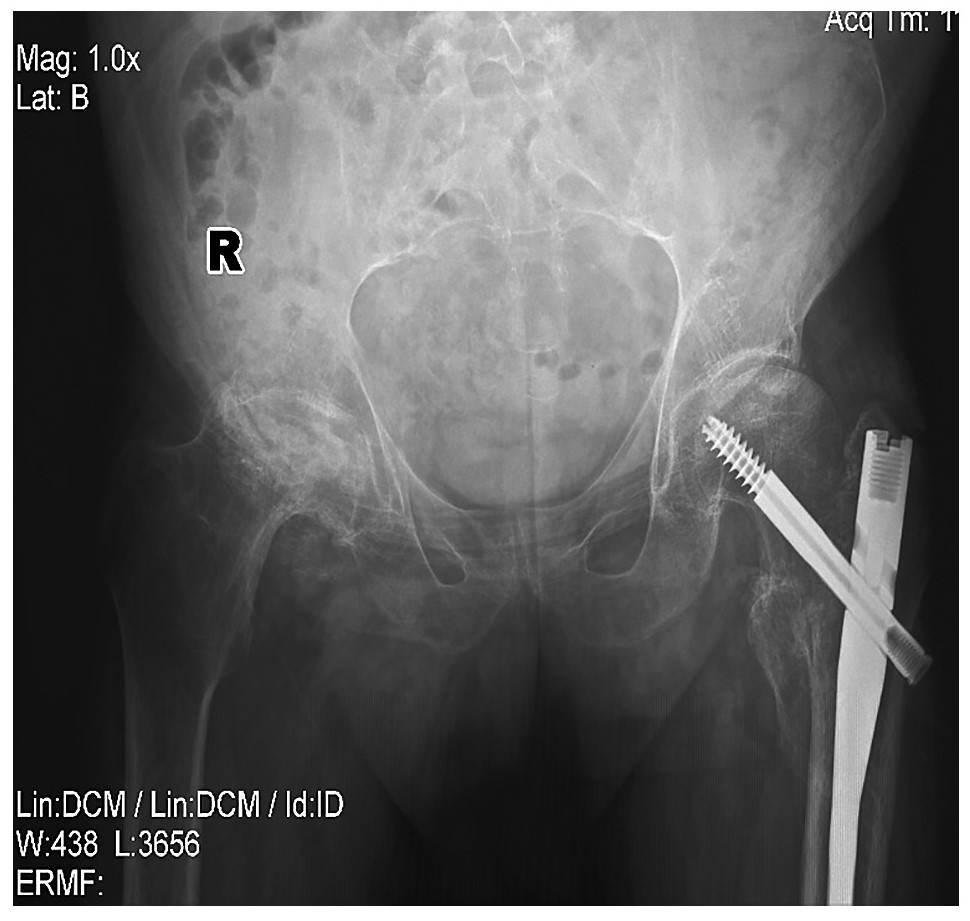

При объективном осмотре выявлен слабоположительный признак поперечной сдавливаемости кистей и стоп. При пальпации остистых отростков позвоночника отмечается болезненность. Сомнительный признак Кушелевского. Обнаружена болезненность при пальпации ахилловых сухожилий. Дактилиты III и I пальцев на левой кисти. Ограничение подвижности в плечевых и локтевых суставах. МТ пациента – 94 кг, рост – 166 см, ИМТ – 34,1, ОТ – 112 см. В лабораторных тестах уровень гемоглобина составил 107 г/л, скорость оседания эритроцитов (СОЭ) – 41 мм/ч, уровень СРБ – 66 мг/л, уровень глюкозы – 7,2 ммоль/л, уровни аспартатаминотрансферазы и аланинаминотрансферазы – в пределах нормы. Индекс Хома – 2,9. Гепатоспленомегалии по данным ультразвукового исследования не выявлено. Рентгенография таза с оценкой ТБС показала наличие состояния после интрамедуллярного остеосинтеза левой бедренной кости (рис. 1). Неполностью консолидированный межпозвонковый перелом. Остеоартроз левого ТБС 3-й степени. Асептический некроз головки правой бедренной кости в стадии фрагментации. Магнитно-резонансная томография (МРТ) грудного отдела позвоночника позволила выявить снижение высоты позвонков ThVII, ThVIII с умеренным отеком костного мозга в позвонке ThVII и формированием углового кифоза.

Рис. 1. Состояние после интрамедуллярного протезирования левой бедренной кости.

Fig. 1. Condition after intramedullary prosthesis of the left femoral bone.

В октябре пациент поступил для продолжения терапии ГИБП на фоне отсутствия обострения симптомов псориаза, несмотря на перерыв в приеме препаратов ГИБП. При объективном обследовании не выявлено симптомов поперечного сжатия кистей и стоп, остистые отростки позвоночника пальпаторно безболезненны, симптом Кушелевского 1-й степени отрицательный. Дактилиты III и I пальцев левой кисти находились в ремиссии. Ограничения в объеме движений в плечевых и локтевых суставах отсутствовали. Наблюдалась положительная динамика как по течению ПсА, так и по показателям лабораторных исследований: СОЭ – 6 мм/ч, СРБ – 10 мг/л, глюкоза – 5,8 ммоль/л, а также по показателям МС. Отмечены дальнейшее снижение МТ, ИМТ, ОТ, нормализация АД и гликемии натощак (см. рис. 1).